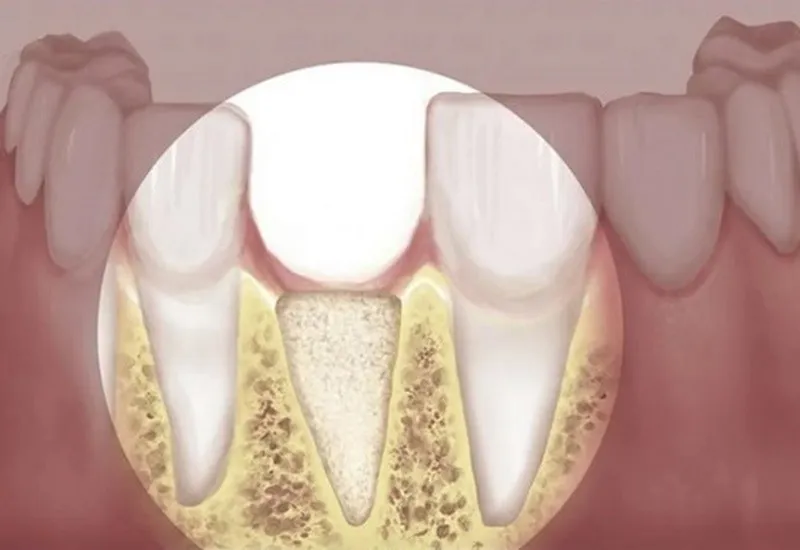

Tiêu xương hàm là hiện tượng nhiều người gặp phải khi bị mất răng. Hiện tượng này nếu để lâu có thể dẫn đến việc bị tụt